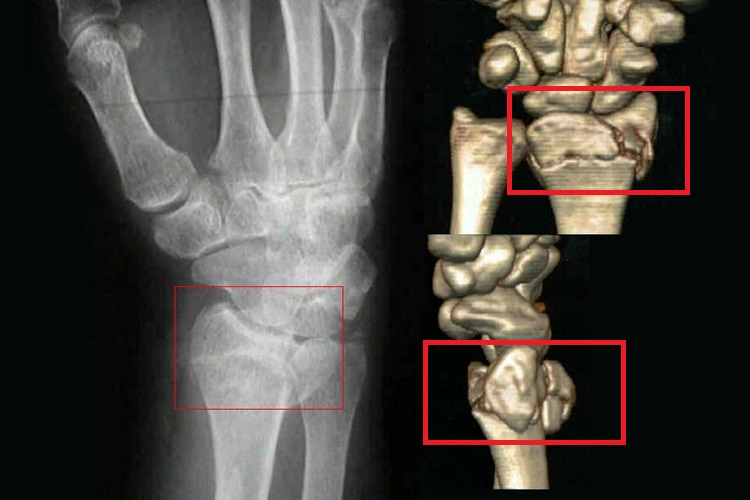

巴通氏骨折属于桡骨远端骨折的一种类型,通过X线等影像学检查可见骨折位于桡骨远端背侧缘,骨折线自桡骨远端关节面上1/3处斜向背侧,骨折块呈楔形,向背侧及近侧移位,腕关节呈半脱位状。同时患者具有腕部肿胀、疼痛、桡骨远端压痛剧烈、腕部畸形明显、活动受限等症状。